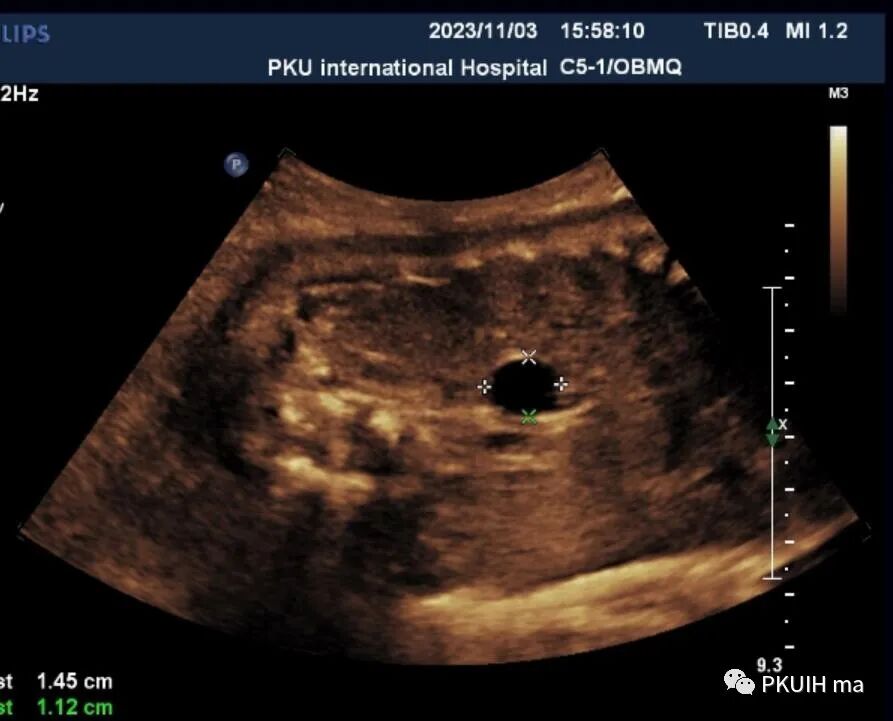

孕妇在之前超声检查中均未见异常,在28周常规超声筛查中发现右侧肾上腺区见一囊肿回声,大小约1.3x1.0cm。随访观察中发现囊肿逐渐增大,胎儿其他各项指标未见明显异常。目前仍在定期随访中